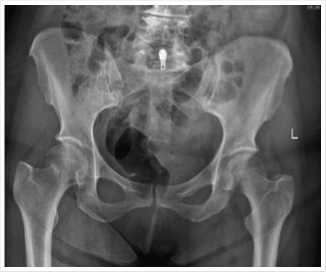

Через 1,5 месяца больная 65 лет доставлена бригадой скорой медицинской помощи в приемное отделения 12.01.2023 г. с жалобами на боль и невозможность наступить на правую нижнюю конечность. Из анамнеза травма получена в результате падения на правое бедро с высоты собственного роста. В приемном отделении осмотрена травматологом. При осмотре выраженная отечность верхней трети правого бедра. Патологическая подвижность. Наружная ротация конечности. Пальпаторно определяется выраженная болезненность верхней трети правого бедра. Отмечается положительный симптом прилипшей пятки. Пассивные и активные движения резко болезненны. Пульсация на сосудах нижней конечности не ослаблен, чувствительность не нарушена. Больная, госпитализирована в травматологическое отделение. На рентгенографии костей таза выявлен подвертельный периимплант-ный перелом правой бедренной кости со смещением отломков (Рис. 3).

Рис 3. Рентгенограмма тазобедренных суставов больной на момент поступления.